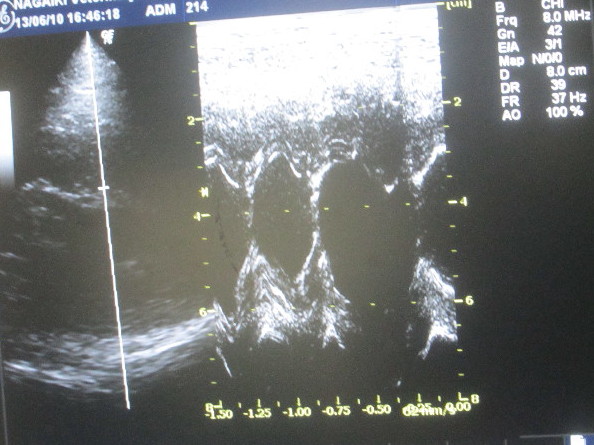

で、本日のメイン診療は『心臓』

前にも使った事のある、『心臓用エコーちゃぶ台』に横になってのエコー。

ベベちゃんと違ってもいちゃんは押さえていないとならないので大変です(ToT)ゞ

結果は今回も異常なし! 良かったぁ〜d(^0^)b Good!!